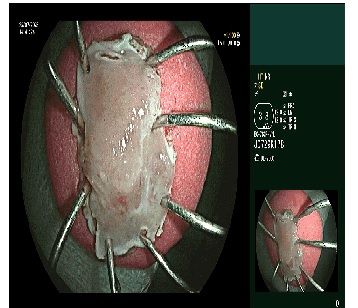

Can thiệp nội soi cắt tách niêm mạc ống tiêu hóa ESD để loại bỏ tổn thương thực quản.

Trước ca lâm sàng phức tạp, kíp bác sĩ khoa Thăm dò chức năng đã tiến hành can thiệp nội soi cắt tách niêm mạc ống tiêu hóa ESD để loại bỏ tổn thương thực quản. Kết quả giải phẫu bệnh xác định đây là ung thư biểu mô vảy tại chỗ, giai đoạn sớm của ung thư thực quản. Đây là kỹ thuật tiên tiến, ít xâm lấn, cho phép lấy trọn tổn thương ung thư giai đoạn sớm mà không cần phẫu thuật. Sau khi kiểm soát khối u thực quản, bệnh nhân được tiếp tục chỉ định phẫu thuật nội soi cắt đoạn trực tràng chứa khối u sigma kèm nạo vét hạch.